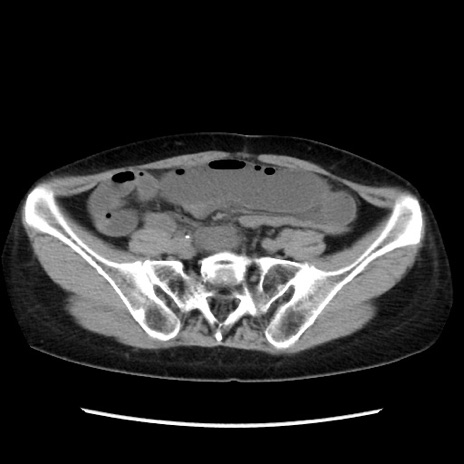

症例32(横断像)

【症例】40歳代 女性

【主訴】上腹部痛、嘔気・嘔吐

【現病歴】約9時間前頃から急に上腹部痛、嘔気、嘔吐が出現。改善しないため救急要請。

【既往歴】子宮頚癌(広汎子宮全摘術、放射線療法)、腸閉塞

【身体所見】腹部:平坦、軟、腸雑音亢進、上腹部を中心に腹部全体に圧痛あり。

【データ】WBC 8400、CRP 0.03